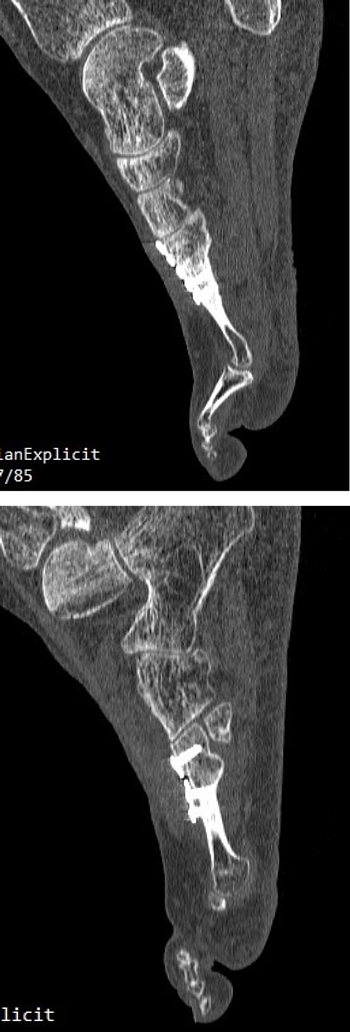

A los 5 meses de la intervención se solicitó nuevamente un TAC comparativo que se realizó el 20 de noviembre de 2015 (Figura 6) que evidenció la integración completa del injerto y la consolidación del 4.º metatarsiano. La evolución clínica de la paciente fue muy positiva con ausencia completa de dolor realizando todas las actividades de la vida diaria con normalidad. Con fecha 25 de mayo de 2016 (11 meses postoperatorios) se realizó última visita de la paciente encontrándose esta en perfectas condiciones y dando el alta a la paciente. La paciente ha sido seguido posteriormente con revisiones anuales durante 4 años (hasta 2019) sin ninguna alteración.

Imagen 6. TAC postoperatorio a los 5 meses. 6A. Imagen del 2º metatarsiano que muestra integración del injerto con la placa dorsal. 6B. Imagen del 4º metatarsiano que muestra consolidación del 4º metatarsiano.